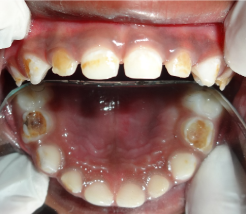

Intra oral examination of the patient revealed number of teeth as 20 with flush terminal plane molar relation, hypocalcified enamel in 53, 52, 63, 62, poor oral hygiene & viscous saliva (Figure 2a-2c). OPG revealed root resorption in 85 which was confirmed with IOPA. IOPA of 74, 84, 75, 85, 54, and 64 revealed radiolucency approximating the pulp.

Figure 2a. Clinical picture representing the anterior teeth. Note enamel wear in 52,53,62,63

Figure 2b. Intra oral picture showing maxillary arch.

Figure 2c. Intra oral picture of Mandibular arch with dental caries in 74,75,84&85.